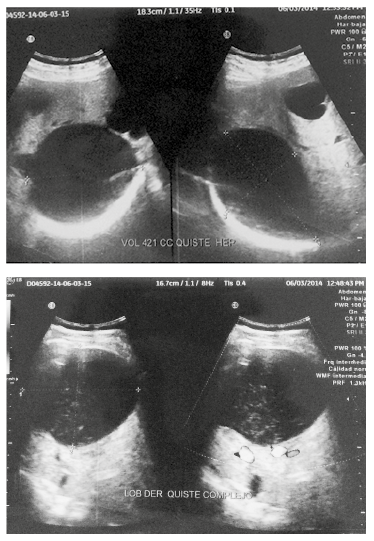

El hemograma mostró glóbulos rojos 4.240.000, hemoglobina 12,2, y hematocrito 36,4; glóbulos blancos 9.400, neutrófilos 45,0%, linfocitos 32,3%, ALT 73 (), AST 39 (), fosfatasa alcalina 76, bilirrubina total 0,4, bilirrubina directa 0,1, bilirrubina indirecta 0.30, GGT 35, tiempo de protrombina 13,5, alfa feto proteína normal. La ecografía abdominal informa hígado con incremento difuso de su ecogenicidad, como se observa en la esteatosis hepática moderada, de aspecto heterogéneo dado por la presencia de varios quistes. El de mayor tamaño mide 10 x 8,5 cm, de paredes regulares con detritus en su interior, tiene un volumen aproximado de 421 cc, avascular al doppler color; en el segmento VII observamos dos quistes simples de 2,5 x 2,8 cm y 2,1 x 1,5 cm, en lóbulo izquierdo observamos nódulo sólido hipoecogénico que mide 2,6 x 2,2 cm, no se observa vascularización de la lesión, no dilatación de vías biliares intra ni extrahepáticas., paciente colecistectomizada (Figuras 1 y 2).